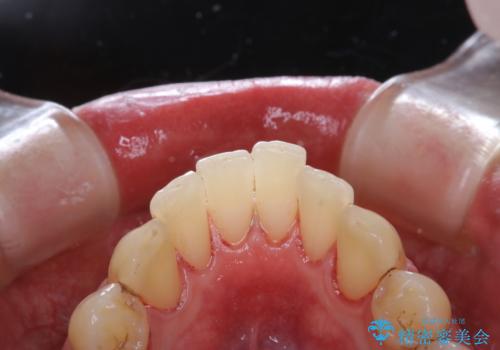

- かなり久しぶりの来院とのことで、クリーニング希望でした。全体的に汚れの付着があったため、PMTCの60分コースを行いました。

PMTCとは、プロフェッショナル・メカニカル・トゥース・クリーニングという、専門家による機械的な歯のクリーニングです。 PMTCは、歯磨きだけでは落とすことのできない細菌・バイオフィルムを除去することが目的です。

歯の健康を守るためには、1回だけで終わらすことなく、定期的にPMTCを行うことがとても大切です。